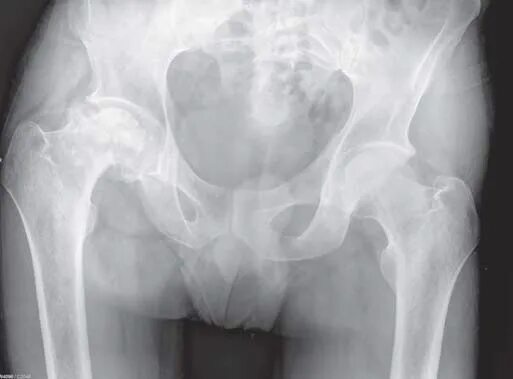

Коксартроз тазобедренного 1 стадии